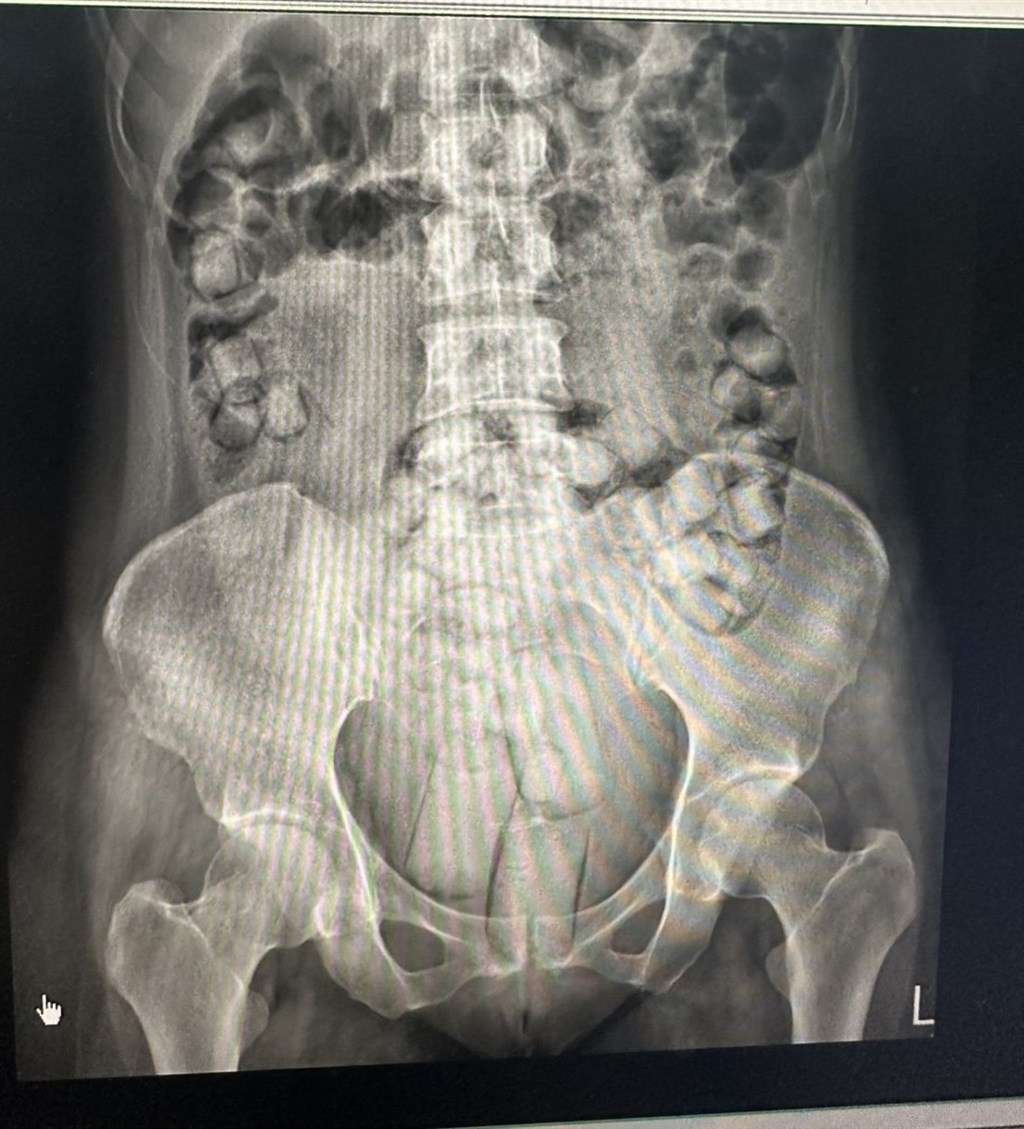

當天下午2人抵達小港機場入境關口時,遭專案小組查獲,照X光發現體內均有大量塊狀物體,經排出檢測呈海洛因反應,估計這批毒品市價約新台幣830萬元,約可供2.5萬人吸食。